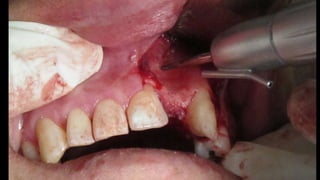

El documento trata sobre la cirugía bucal para plastía del proceso alveolar utilizando hueso humano y factores de crecimiento. También menciona los cuidados postoperatorios, que incluyen el uso de hielo, reposo, dieta líquida y antibióticos, evitando antiinflamatorios no esteroides. Se proporciona información adicional sobre las páginas web relacionadas con cirugía maxilofacial.